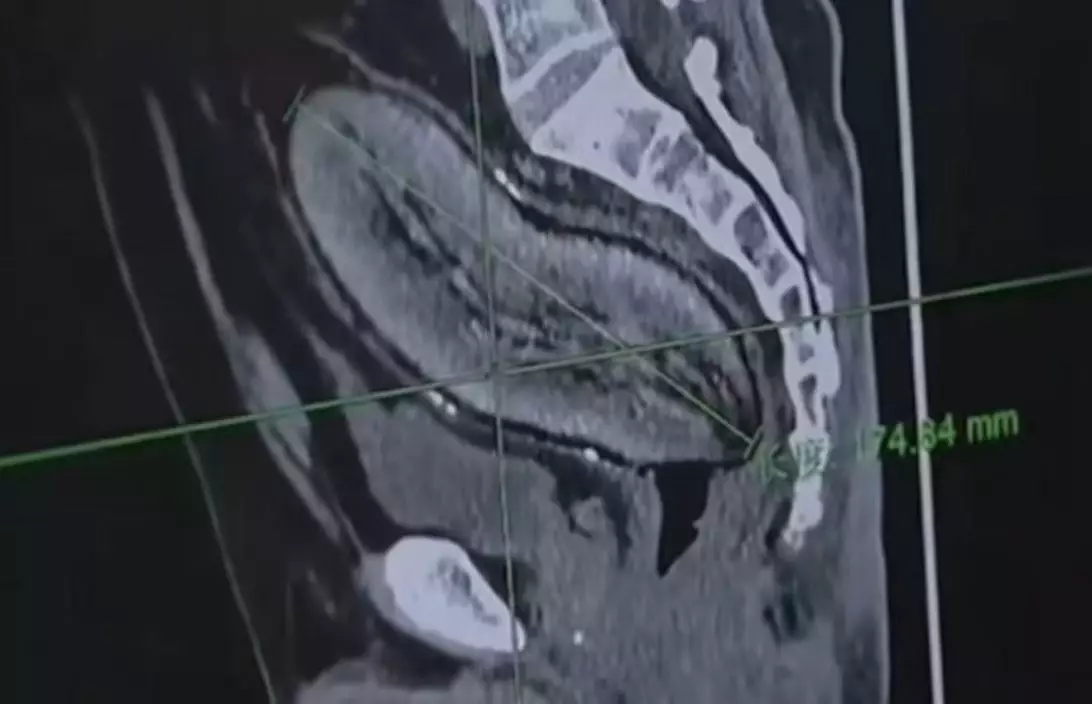

綜合內媒報導,甘肅定西一名28歲田姓女子自幼患有罕見「面部神經纖維瘤」,一直以來備受病患折磨。儘管先後接受5次手術,腫瘤仍存有復發及惡化風險。多年來累計醫療費用逾數十萬元人民幣,左眼視力也近乎喪失。由於腫瘤體積龐大,不但嚴重影響外觀,也干擾日常生活,令她長期承受巨大壓力。

醫生評估指出,孕激素可能刺激腫瘤增生,意味懷孕等生理變化或會導致病情加劇。神經纖維瘤屬源自周邊神經組織的良性腫瘤,可生長於皮膚、皮下組織,或沿神經叢深入更深層部位。